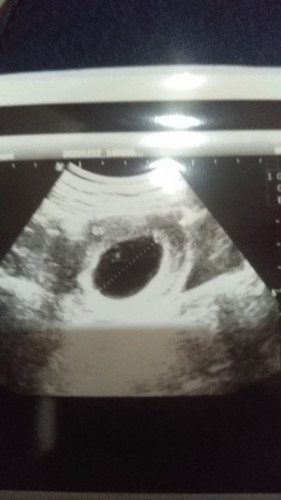

Apa kehamilan BO bisa dinusahakan untuk normal , aku habis usg tapi hasilnya sangat membuat sedih .

kalo BO jelas harus d kuret atau minum penggugur dr dokter. harusnya BO tdk berulang tp klo d kehamilan selanjutnya BO lg harus periksa lanjutan tuh utk faktor BOnya apa

saya dulu pernah BO bun, di usia kandungan masuk 4 bulan di kiret manual...